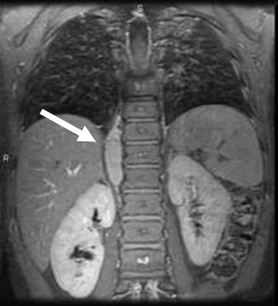

CT scan of the abdomen showing paraspinal neuroblastoma

From the personal collection of Dr Jason Shohet